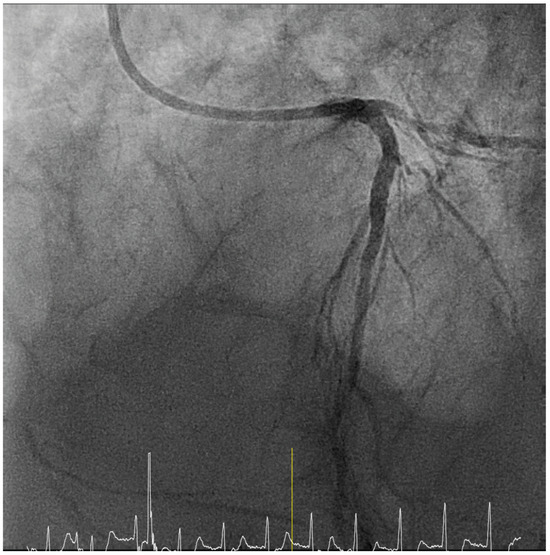

When the Chest Pain Suddenly Worsens

Case presentation

Solution